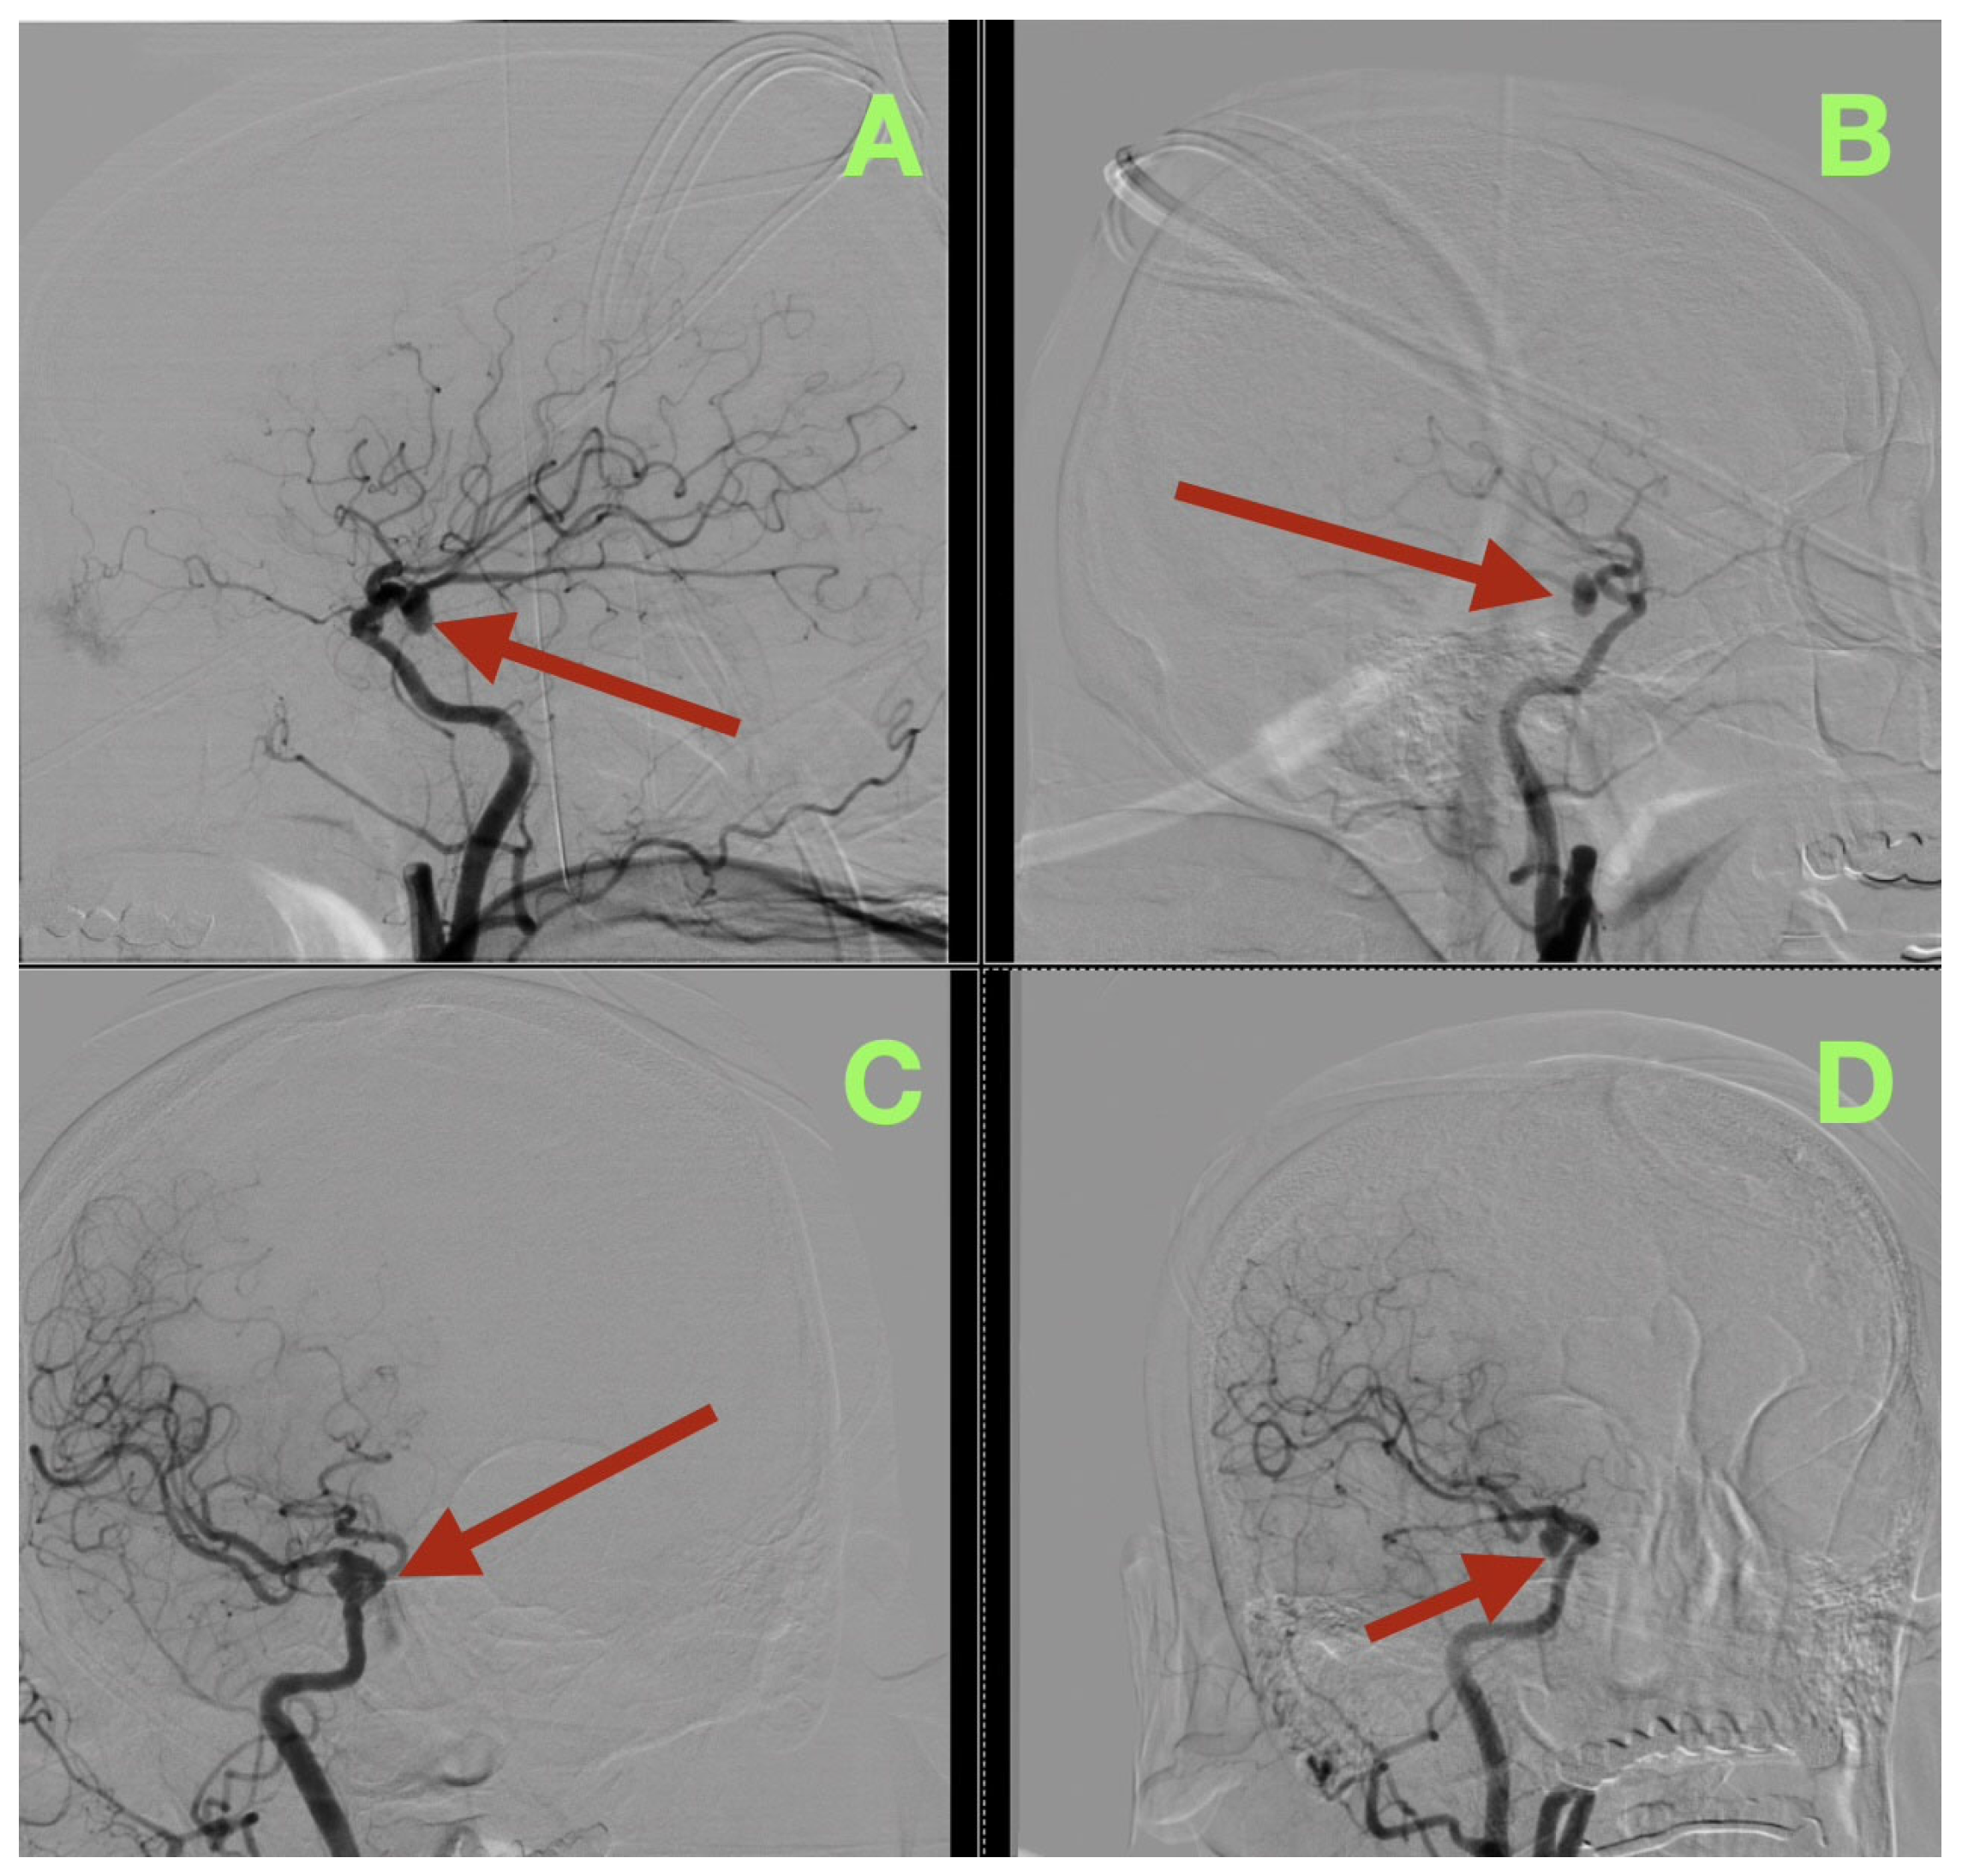

The first image obtained was a non-contrast cranial CT, which showed that there was an SAH (Fisher grade 4), hemorrhage into the ventricles of the brain, and generalized cerebral edema, along with evidence suggesting that the patient had acute hydrocephalus. Due to this verified hemorrhage pattern and significant risk of rebleeding, the patient underwent physiologic stabilization as part of the preoperative process; the patient was intubated and maintained a PaCO2 level between 35 and 38 mmHg to avoid hypercapnic related intracranial hypertension, and the patient’s arterial blood pressure was continuously monitored using nicardipine to keep the systolic blood pressure between 110 and 130 mmHg to decrease the risk of rebleeding while maintaining adequate cerebral perfusion. Selective right internal carotid artery angiography, including DSA, confirmed a saccular aneurysm located at the posterior communicating segment of the right internal carotid artery with a posteriorly oriented dome and a very narrow neck (<3 mm); the aneurysm arose from a branch critical area where a fetal type posterior cerebral artery (fPCA) branched off the aneurysm neck plane (Figure 1A–D). The presence of the aneurysm at a branch critical area made it necessary to reconstruct the junction of the aneurysm neck to the parent vessel, versus simply closing the aneurysm neck to preserve the lumen of the fPCA. Three-dimensional rotational angiography further defined the operative geometry and confirmed the aneurysm’s neck diameter to be approximately 2.5 mm and the maximum sac diameters to be approximately 7.7 × 6.6 mm (Figure 2C,D). The aneurysm was located at the carotid–PCom junction and was closely associated with the oculomotor cisternal corridor providing a potential anatomic basis for the intermittent pupillary variability observed during the acute phase of hemorrhage.

Figure 1.

Preoperative digital subtraction angiography (DSA). (A) Selective right internal carotid injection in a lateral projection demonstrates a posteriorly directed saccular aneurysm arising from the communicating segment (arrow), seated at the carotid–posterior communicating region. (B) Oblique projection confirms posterior dome projection (arrow) and refines the profile of the aneurysm base at the junctional complex. (C) Complementary lateral/oblique acquisition delineates the compact neck architecture (arrow), supporting a focal saccular morphology rather than fusiform dilation. (D) Anteroposterior projection provides orthogonal confirmation of lesion position (arrow) at the right carotid communicating segment, validating neck definition and dome directionality across planes.